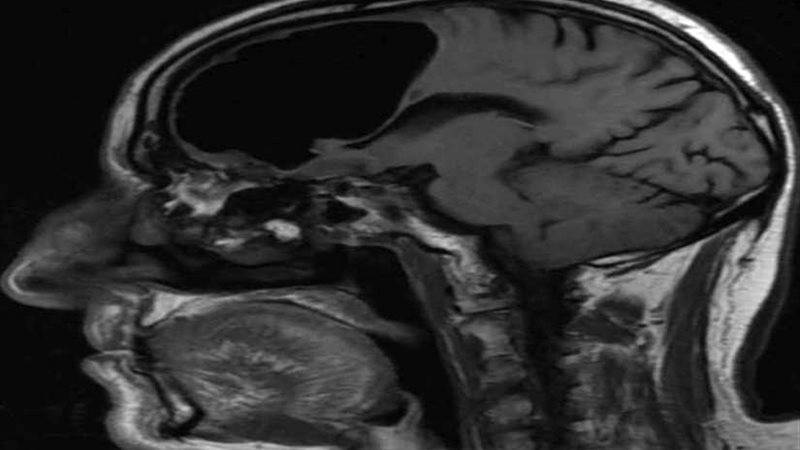

وقالت " روسيا اليوم: "اكتشف الأطباء وجود "تجويف هوائي" يبلغ طوله 10 سنتيمترات في النصف الأيمن من دماغ رجل مسن نقل إلى المستشفى عقب شعوره بالدوار وسقوطه على الأرض، بعد أن تبددت شكوكهم بإصابته بسكتة دماغية.

وبينت نتائج التصوير بالرنين المغناطيسي لدماغ الرجل المسن، وجود ما يسمى بالفتق الهوائي وهو ما يلاحظ عادة لدى المرضى الذين يعانون من إصابات في أجزاء معيّنة من الجسم والأعضاء الداخلية.

كما كشف الفحص وجود ورم عظمي "تشكّل حميد في عظام الوجه يفصل بين تجويف الأنف والدماغ"، دخل من خلاله الهواء إلى دماغ الرجل وبقي فيه لعقود من الزمن، ما أدى إلى الضغط على الدماغ وتعطيل التنسيق في بعض وظائفه الحيوية، وهذا ما أدى إلى شكوى الرجل من الدوار المتكرر.